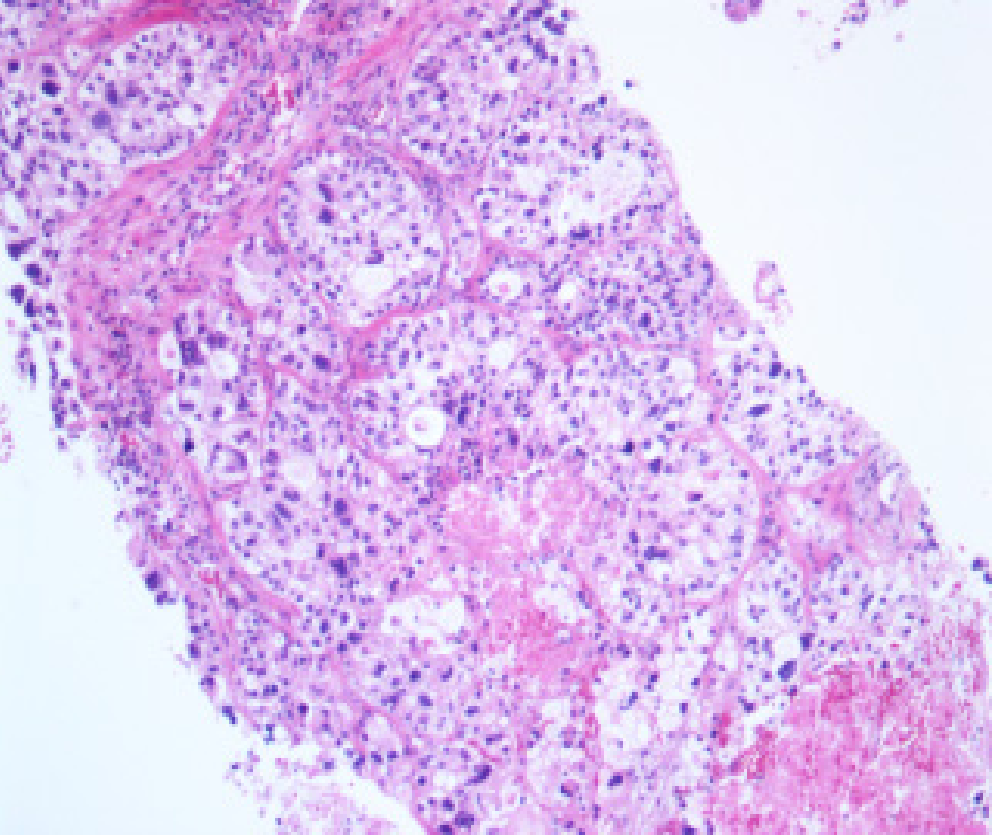

CT引导下肺占位穿刺标本

大体描述:肺占位穿刺标本:活检送检灰白组织2条,长0.7-1.3CM,直径0.1CM,全取。

病理诊断:(肺占位穿刺标本)腺癌。

免疫组化染色结果:A:TTF-1(+)、NapsinA(+)、CK7(+)、ALK(-)、Ki67(+,10%)。